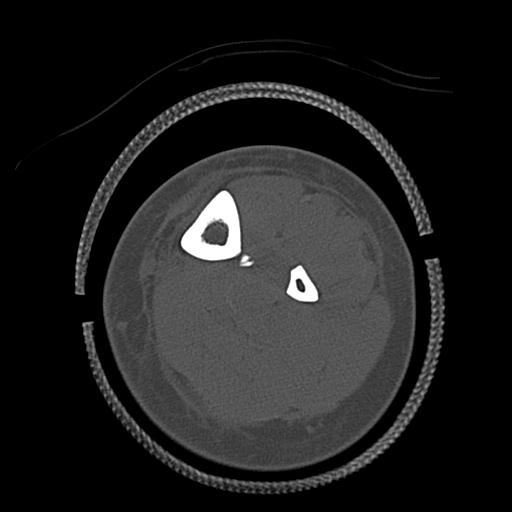

56476 8/28 4R 1/21 2R 左足関節 デジカメ写真 72歳女性 右足関節AS